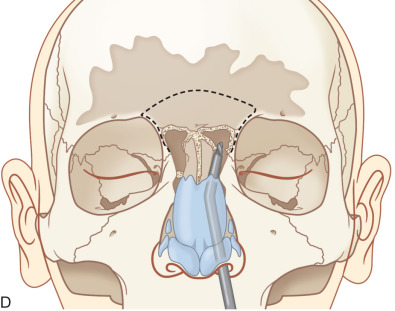

A transnasal endoscopic frontal sinusotomy (or Draf III procedure) is commonly used for management of chronic frontal sinusitis, mucoceles, frontal sinus trauma, and frontal sinus tumors. It provides access to the frontal recess as well as the anterior and posterior table of the frontal sinus. The procedure begins with an endoscopic ethmoidectomy and identification of the ethmoid skull base and lamina papyracea ( Fig. 1.7.12A ). Utilizing angled endoscopes (30, 45, or 70 degree depending on surgeon preference) and through cutting instrumentation, the floor, posterior wall, and roof of the agger nasi cell are removed. The frontal recess has now been dissected and an endoscopic view of the frontal sinus is achieved. The same procedure is then performed on the contralateral side until the bilateral frontal sinus ostia are visible. A 2 × 2 cm superior septectomy is then performed to gain bilateral access to the floor of the frontal sinus ( Fig. 1.7.12B ). The posterior limit of this window should align with the anterior aspect of the middle turbinate. The septal window is lowered until the opposite frontal recess and upper half of the opposing middle turbinate is visible. The septal mucosa is harvested and preserved as it may later be used for mucosal grafting of the exposed bone of the frontal beak. Utilizing a high-speed, angled 4 mm diamond bur, the bone of the septum is removed to identify the floor of the frontal sinus ( Fig. 1.7.12C ). The posterior limit of this dissection is the first olfactory neuron. The axilla of the middle turbinate (i.e., frontal process of the maxilla) is demucosalized and drilling proceeds from lateral to medial, removing the bone of the axilla and identifying the periosteum of the underlying skin ( Fig. 1.7.12D ). This marks the lateral limit of the dissection. The floor of the frontal sinus is then removed to create a large horseshoe-shaped neostium. The nasofrontal beak is thinned utilizing a 70 degree bur and 30 degree endoscope. The frontal intersinus septum is partially removed to create a median drainage pathway for the frontal sinus ( Fig. 1.7.12E ). The exposed bone of the frontal beak may be left bare, dressed with Silastic sheeting, or grafted with septal mucosa harvested from the creation of the septal window.